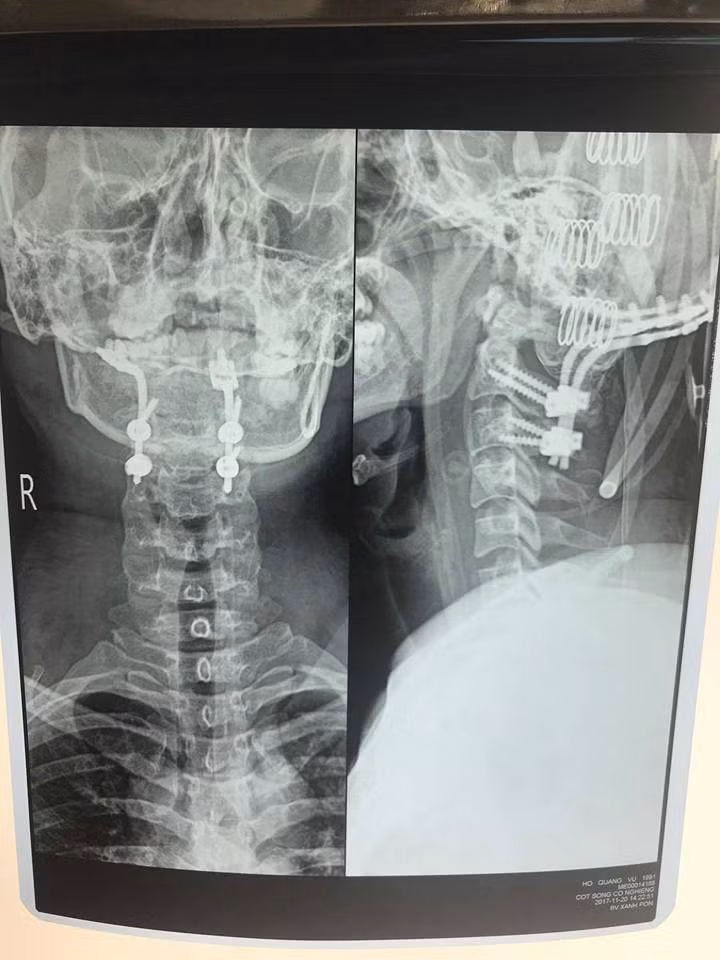

Tại Bệnh viện Xanh Pôn, các bác sĩ ngay lập tức cho bệnh nhân chụp CT cột sống cổ. Hình ảnh cắt lớp vi tính cột sống cổ cho thấy hình ảnh phù nề nặng phần mềm trước sống, trật khớp chẩm đội, trật đốt sống C1C2.

Hình ảnh trật đốt sống cổ của bệnh nhân